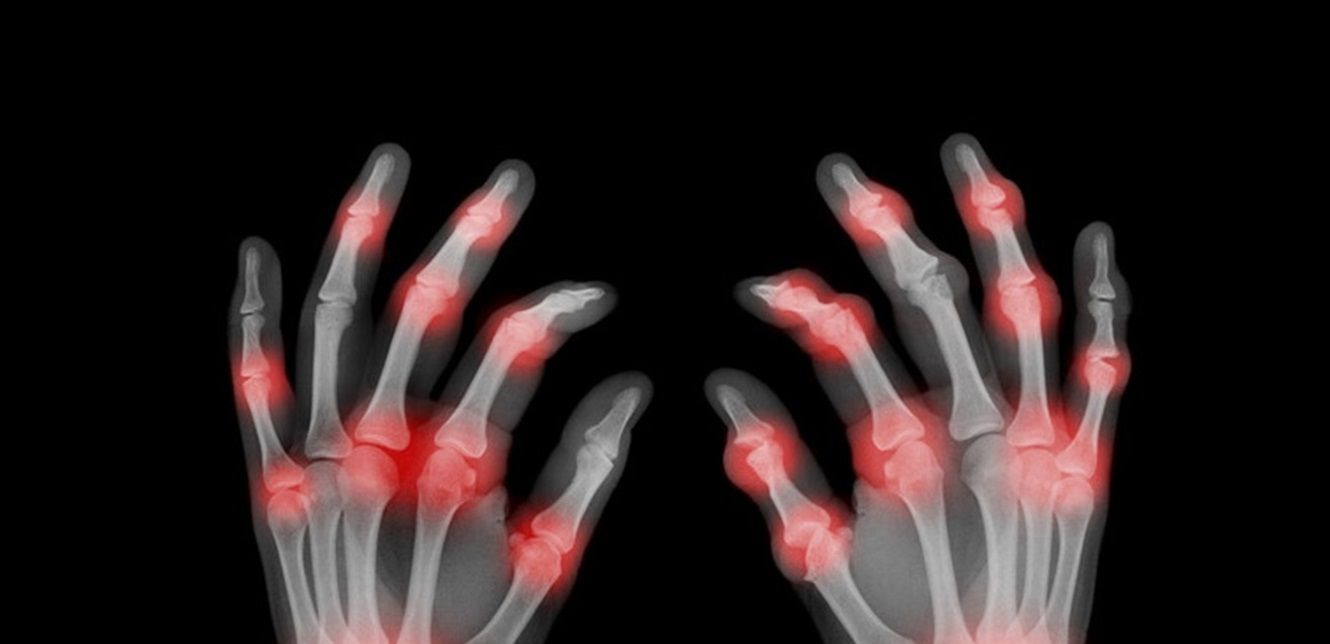

ويؤثر هذه الاضطراب النادر للغاية على مشاشات العظم (النهاية المستديرة للعظام الطويلة)، ويمتاز بقصر القامة مع جذع قصير، ويتسبب في صعوبة في المشي وألم وتصلب في المفاصل، وأصابع قصيرة.